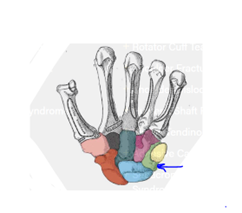

1. Which bone is marked here?

1. Trapezoid

2. Trapezium

3. Triquetrum

4. Pisiform